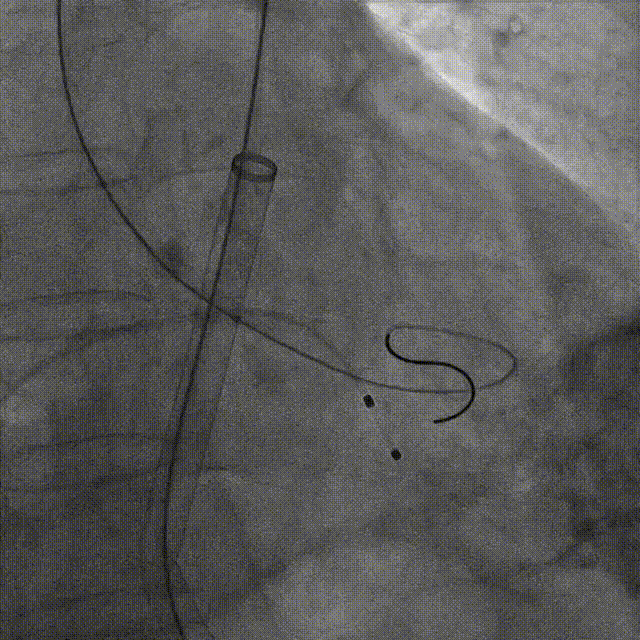

宋光远教授 首都医科大学附属北京安贞医院(点击查看专家详细简历) 技术革新不止,创新求索不辍:一切从患者出发,不断追求创新是内心的坚定。当年‘ALL IN ONE’的探索,正是怀揣着这份初心 —— 通过整合器械与操作,将入路创伤缩至最小,让患者在微创中更快康复,这是技术对患者的温柔承诺。而术中脑保护,是我们为安全筑牢的另一道防线。 此次预装干瓣的临床应用,让我们直面瓣膜“耐久性“临床困境,期待创新技术助力全生命周期管理! 病例概览 患者病史 患者因 “劳力性呼吸困难半年余,加重 20 天” 入院。高血压病史 20 年,最高血压 160/110mmHg;高脂血症病史;反流性食管炎。 超声提示:主动脉流速 Vmax 4.66 m/s,平均压差 53mmHg,左室射血分数(LVEF)40%; 超声诊断:主动脉瓣狭窄(重度)、主动脉瓣反流(轻中度)、二尖瓣狭窄(轻度)、二尖瓣反流(轻度)、三尖瓣反流(轻中度)、左房增大,左室肥厚。 术前CT 瓣环(Annulus)直径:22.9mm,左室流出道(LVOT)直径:周长径 23.8mm;总钙化负荷1239mm³(HU850),钙化集中于无冠窦,且蔓延至 LVOT,呈重度钙化表现;LVOT-Annulus 呈微直筒型,瓣上限制较重。左冠脉开口高度略低,瓣叶不长、窦部空间较大,结合钙化分部情况,预估双侧冠脉遮挡风险较低。室间隔膜部较短(2.4mm)有一定PPI风险,心室大小可,心脏角度64°,升主长度短于胶囊腔长度,同轴有一定困难。 · 造影角度及入路情况:主动脉弓角度可,但降主动脉折曲明显,双侧髂股动脉存在粥样硬化。 手术策略 采用 “极简式” 手术方案:18/20mm 球囊预扩张,植入金仕生物 Prostyle-A 预装干瓣(AV 26),配合长鞘,同时植入脑保护装置以降低卒中风险。 手术过程 球囊预扩:18号球囊预扩 输送系统顺利过弓跨瓣: 瓣膜植入:工作位观察位置适宜,完成植入。 术后即刻:术后造影显示瓣膜位置佳 入路与血管:撤出大鞘后检查,降主动脉仍存在较大弯折;入路闭合良好,无明显出血或血管并发症。 Prostyle A®预装干瓣——助力临床最优化解决方案: √ Mircro-EX™专利抗钙化技术:极简式预装干瓣,不使用戊二醛浸泡,减少钙化成因,干态存储的瓣膜术中无需清洗瓣膜,减少组装步骤,缩短手术时间,尤其适合复杂病例中的高效操作; √ 平衡的径向支撑力:重度钙化的患者,形态展开良好,在横位心等复杂情况下实现稳定锚定及释放; 专家简介 苑飞 首都医科大学附属北京安贞医院(点击查看专家详细简历) 姚晶 首都医科大学附属北京安贞医院(点击查看专家详细简历) · END ·